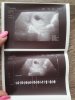

Lekarz twierdzi, że wszystko w najlepszym porządku![]()

Według OM ? Ciąża może być młodsza i tego się trzymaj , poczekaj tydzień ... zrób ponowne usg , na tym etapie każdy dzień to mogą być spore zmiany w UsgDziś 6+4 więc powinno coś być a tu dupa

Tak wg OM i lekarz powiedział że tak będziemy ta ciążę liczyć.dalek mam brać witaminy i luteinę.Według OM ? Ciąża może być młodsza i tego się trzymaj , poczekaj tydzień ... zrób ponowne usg , na tym etapie każdy dzień to mogą być spore zmiany w Usg

Zobaczysz że pojawi się fasoleczka z serduszkiem bijącym tego Ci życzę z całych sił i w to wierzęTak wg OM i lekarz powiedział że tak będziemy ta ciążę liczyć.dalek mam brać witaminy i luteinę.

Wiem że trudno ci będzie ale odpocznij od internetu od forum.Pierwsza ciąża, dziś 6+4